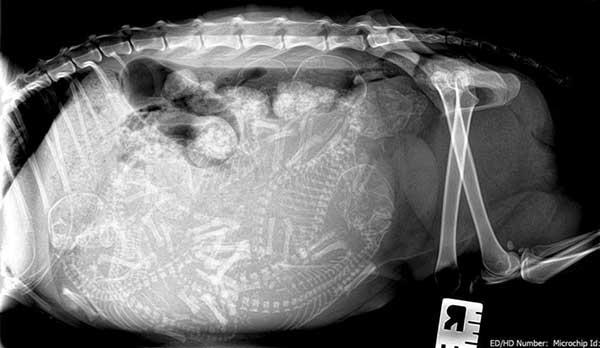

Необходимым моментом в этом периоде беременности является проведение рентгенографии и УЗИ. Целью этой процедуры является изучение информации о количестве плодов и их размещении в матке. И если некоторые котята находятся в неправильном положении, то это надо будет учитывать при родах.